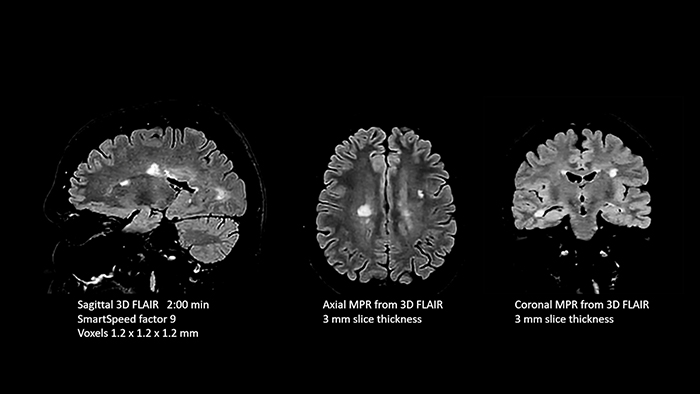

Improving diagnostic confidence across the board at MRT-Praxis Potsdam

Dr. Schröter points out that a more confident diagnosis requires high-quality images with more diagnostic information. “Philips SmartSpeed provided that to us. AI denoises the clinical images without losing any important data, resulting in high-resolution images. It keeps all the information we need and makes the images better.

We can apply SmartSpeed to almost all sequences. That is a big step forward! We use it for example in 3D imaging and in diffusion-weighted imaging, to dramatically reduce scan time or increase image resolution, which is quite useful.

There are small lesions that we would certainly have seen without SmartSpeed, however it would have taken us longer to properly diagnose. In 3D MSK images with extremely high resolution, we uncover the finest anatomical structures and can thus report very detailed findings.”